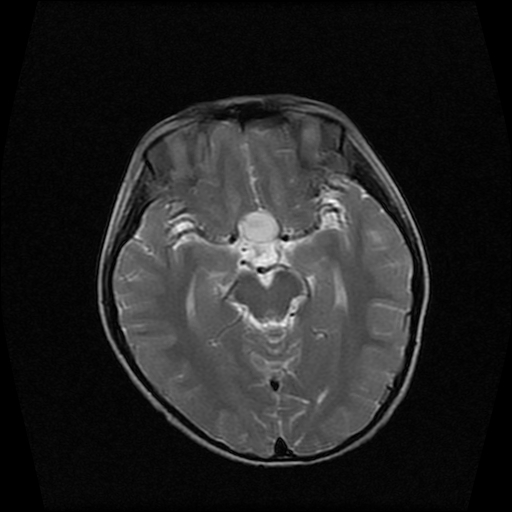

男性,12岁。反复头痛呕吐半月。脑积液无异常。病变部位ct值32hu,dwi无异常。

鞍上为主,累及鞍内,垂体受压位于鞍底。mri呈短t1、长t2信号,不太支持生殖细胞肿瘤,首考颅咽管瘤。

鞍内囊性占位性病变,t1wi、t2wi,均为高信号影。ct平扫为等密度。发病年龄较小。故首先考虑颅咽管瘤,可以做ct增强扫描